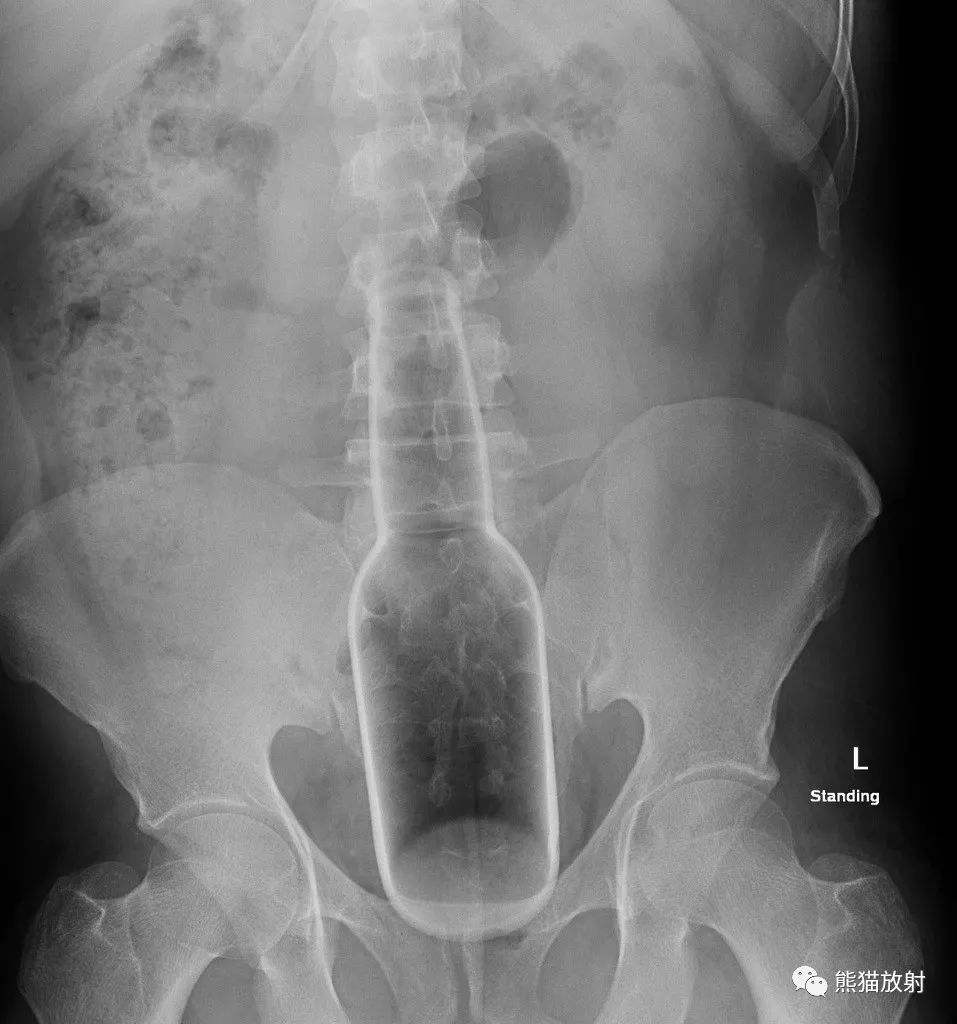

由于**内壁是软组织,而控制**的括约肌不是可以完全由主观控制的,所以刺激**需要多多注意安全。大多数人由于缺乏性知识,还有对社会歧视的恐惧,所以很多人不好意思购买这方面的性玩具,而用手边日常生活用品刺激**,比如一些条状水果,或者柱状、球状的日用品。

在急诊室或放射科工作过的医生都了解这一点。一个放射科协会的网站上展示了很多的案例照片。